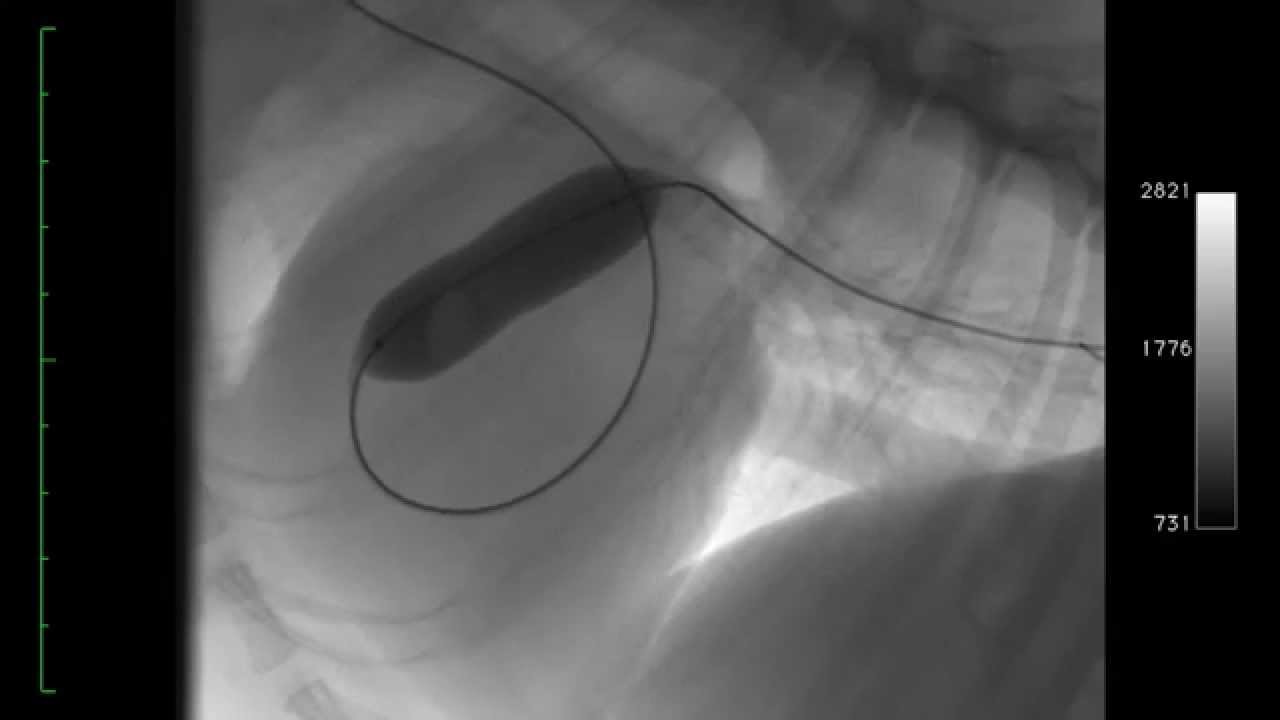

From www.youtube.com

FLUOROSCOPY AND CARDIAC CATHETERISATION DOG YouTube Cost Of Fluoroscopy For Dogs If your pet experiences these signs, we can use fluoroscopy to watch the epiglottis to look for an abnormality it its motion. Luckily, the hospital recommended ella’s fund, which provides grants of up to $1,100 to dog owners in financial need, for dogs with a good prognosis that need life. The same basic design is still used in veterinary medicine. Cost Of Fluoroscopy For Dogs.